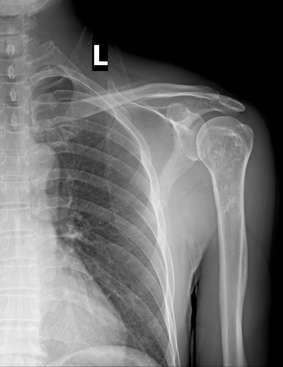

男,50岁,左肩部轻微疼痛,活动不便5个月就诊,无红肿热痛,间断理疗治疗无好转,既往5个月前左肩轻微拉伤史。

肱骨上段髓腔内蜿蜒索条状、簇状高密度影,肱骨头多发囊变。考虑:肩关节周围炎,并肱骨上段骨梗死。

支持骨梗死的诊断,但平片不好诊断,结合临床考虑是肩周炎。但诊断应该是临床诊断的